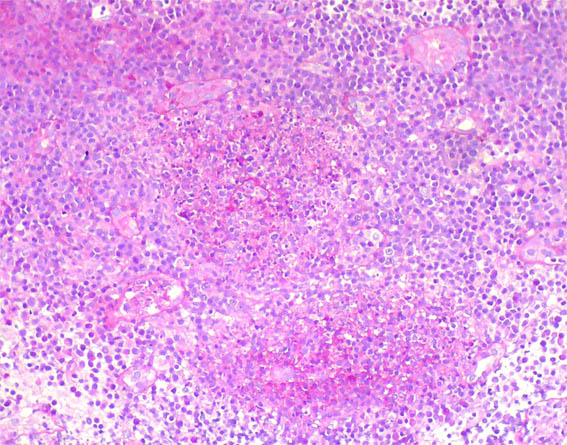

An allograft kidney biopsy was done. See the images.

Figure 4. H&E, X400.